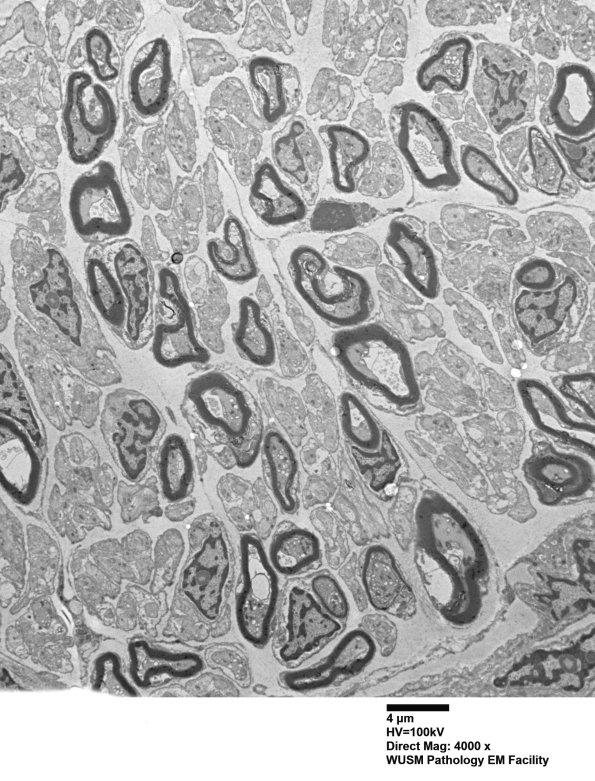

Washington University Experience | PERIPHERAL NEUROPATHY | 1 NORMAL NERVE ANATOMY | 6 Infant Peripheral Nerve | 1B3 (Case 1) EM 003 - Copy

1B3,4 Higher magnification demonstrates that the increased neuropil consists of small non-myelinated axons in copious Schwann cell cytoplasm and some unidentified stromal elements. (electron micrographs)